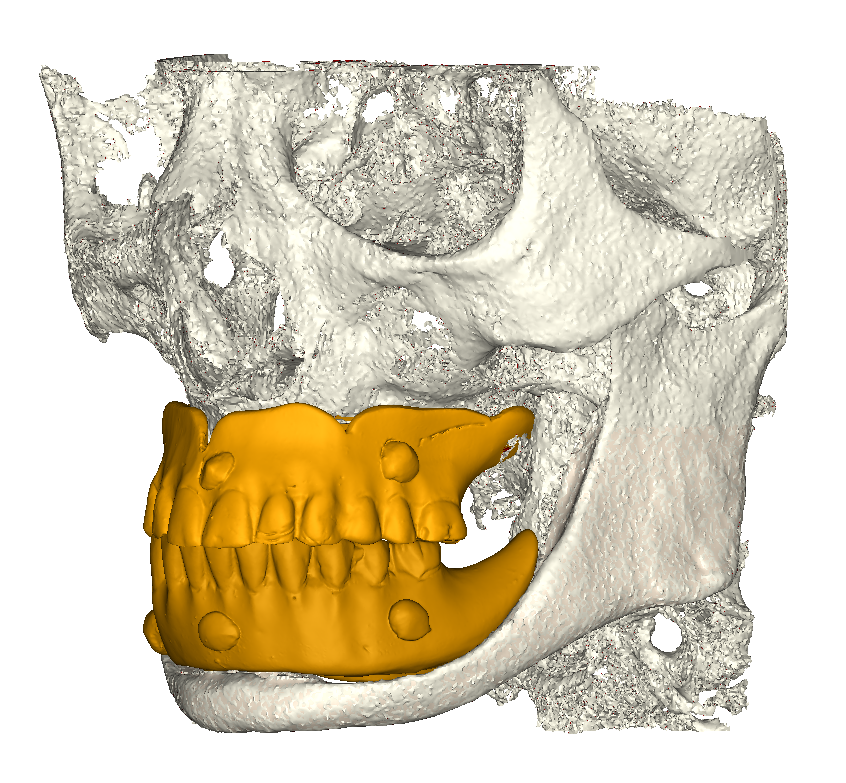

Modello 3D

Fig. 1(b). Modello 3D.